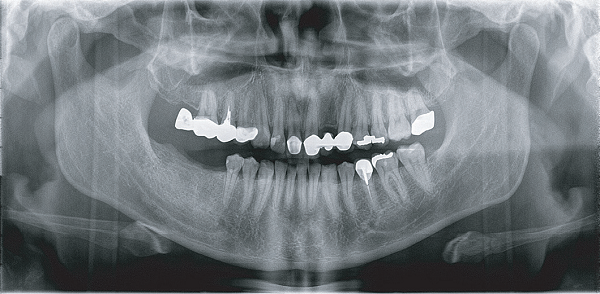

臨 床 圖 集